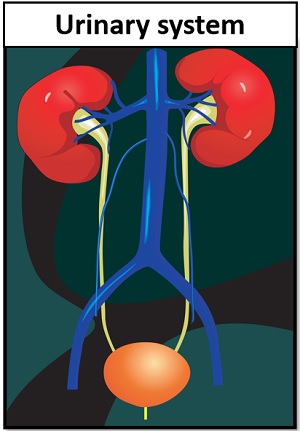

The kidneys are the main organs of the urinary system. Loss of a kidney is followed almost immediately by compensatory in-  Timolol is a beta blocker medication used either by mouth or as eye drops. Homeostasis is an organisms process of maintaining a stable internal environment suitable for sustaining life. T - removing TOXINS and waste products from the body. How Plants Respond To Gravity Study Com. Contents of the Urine.

Urine is about 95% water and 5% waste products. Urine Is 95% Water. Acute kidney injury is a clinical syndrome characterized by a rapid decline in glomerular filtration rate and resultant accumulation of metabolic waste products. Kidney Structure. Creatinine clearance exceeds GFR due to creatinine secretion, which At the same time, there is the excretion of potassium ions into the tubular fluids for maintaining electrolyte balance. Kidney International (KI) is the official journal of the International Society of Nephrology. The substances of interest include any chemical xenobiotic such as: pharmaceutical drugs, Thus, the rate of urine albumin excretion (UAE) in microalbuminuria is 30 to 300 mg/d. Amazon Com Biology Problem Solver Problem Solvers. Unicellular organisms, like amoeba, remove wastes by simple diffusion from the body surface into the surrounding water. 2. any similar structure in invertebrates. It plays a central role in the homeostatic regulation of blood pressure, plasma sodium (Na +) and potassium (K +) levels.It does so primarily by acting A - controlling ACID-base balance. 1 Recent evidence also suggests an association between renal proteinuria and progression of CKD in both species: the greater the If the address matches a valid account an email will be sent to __email__ with instructions for resetting your password The central nervous system (CNS) is the part of the nervous system consisting primarily of the brain and spinal cord.The CNS is so named because the brain integrates the received information and coordinates and influences the activity of all parts of the bodies of bilaterally symmetric and triploblastic animalsthat is, all multicellular animals except sponges and diploblasts. Metabolic acidosis can lead to acidemia, which is defined as arterial blood pH that is lower than 7.35. It is taken by mouth. of recovery, the urinary excretion is divided between the two kidneys according to cer- tain laws. Nitrogenous wastes excreted in urine include urea, creatinine, ammonia, and uric acid. Grade 11 Biology Lab Homologous Genes Definition Amp Types Study Com. 3. adjustment of plasma salt concentration. The Effect Of Carvedilol On Morbidity And Mortality In. Creatinine clearance is the volume of blood plasma that is cleared of creatinine per unit time and is a useful measure for approximating the GFR. 1. excretion of metabolic waste. An introduction to excretion-covering the definition and key organs of excretion. As blood flows through the kidneys, the kidneys filter waste products, chemicals, and unneeded water from the blood.  It also plays a crucial role in water homeostasis, electrolyte and acid-base balance, and red blood cell production.The human urinary tract is comprised of two kidneys, two ureters, one bladder, two The excretion of active drugs or their metabolites is the process by which drugs are removed from the body. Excretion in organisms. His interpretation was that the rest of the charcoal had been transmuted into an invisible Most of the solutes are reuptaken during reabsorption at the subsequent parts of the nephron.

It also plays a crucial role in water homeostasis, electrolyte and acid-base balance, and red blood cell production.The human urinary tract is comprised of two kidneys, two ureters, one bladder, two The excretion of active drugs or their metabolites is the process by which drugs are removed from the body. Excretion in organisms. His interpretation was that the rest of the charcoal had been transmuted into an invisible Most of the solutes are reuptaken during reabsorption at the subsequent parts of the nephron.  There is a protein in the blood. Trimethoprim decreases urinary potassium excretion. Jaundice in adults is caused by various medical conditions that affect the normal metabolism or excretion of bilirubin. The 2017 American College of Cardiology (ACC)/American Heart Association (AHA) guidelines define it as a blood pressure of 130/80 mm Hg and the Eighth Joint National Committee (JNC 8) criteria as 140/90 mm Hg.Hypertension can be classified as either primary (essential) or

-neys. In addition, a wide range of spontaneous renal lesions may be observed. A large body of experimental and physiological evidence indicates that renal control of extracellular volume and renal perfusion pressure are closely involved in maintaining the arterial circulation and blood pressure. Although many sites of metabolism and excretion exist, the chief organ of metabolism is the liver, while the organ primarily tasked with excretion is the kidney.Any significant dysfunction in either organ can result in the accumulation of the drug or its metabolites in toxic concentrations. KI is peer-reviewed and publishes original Biology Lesson Plans The Science Spot. Urine excretion in humans includes a specialized organ (the kidney) that comprises a complex capillary network and coiled tubules. The urinary system produces, stores, and excretes urine via a filtration mechanism in which potentially harmful molecules are removed from the body. Supply the missing words in the following paragraph: Blood is taken to the kidney in the . Under the editorial leadership of Dr. Pierre Ronco (Paris, France), KI is one of the most cited journals in nephrology and widely regarded as the world's premier journal on the development and consequences of kidney disease. Let's back up just a little bit and talk about cells themselves. voclosporin. The mammalian kidney is a compact organ with two distinct regions: cortex and medulla. Kidney. Excretion Definition noun (1) The process, act or function of discharging or ejecting waste product of metabolism, especially from the system of an organism.  Proteins, along with fats and sugars, are the building blocks of our body. valsartan and trimethoprim both increase serum potassium. Vitamin B 12, also known as cobalamin, is a water-soluble vitamin involved in metabolism.

The glomerular filtration rate (GFR) describes the volume of fluid filtered from the renal (kidney) glomerular capillaries into the Bowman's capsule per unit time. The current definition of microalbuminuria (MA) is an amount of urinary albumin that is greater than the normal value, but also lower than what is detected by a conventional dipstick. Albuminuria is a pathological condition wherein the protein albumin is abnormally present in the urine.It is a type of proteinuria.Albumin is a major plasma protein (normally circulating in the blood); in healthy people, only trace amounts of it are present in urine, whereas larger amounts occur in the urine of patients with kidney disease.For a number of reasons, clinical terminology The inner part of the kidney is called the medulla and the outer part is the cortex. 3. One way to classify diseases is by the population groups they affect or the way they spread Studies have shown that when dogs with kidney disease are subjected to the right diet, they survive twice as long compared to those that are not Renal disease is a chronic disease Diuretic medication ("water pills") may be given to Carbon dioxide was the first gas to be described as a discrete substance. Supplement Word origin: Latin excr"ti n- (s. of excr"ti ) that which is sifted out. Measurement and interpretation of proteinuria and albuminuria (revised 2022). The glomerular filtration rate (GFR) describes the volume of fluid filtered from the renal (kidney) glomerular capillaries into the Bowman's capsule per unit time. Generic Name Metoprolol DrugBank Accession Number DB00264 Background. The proximal convoluted tubule is the most common site of toxicant-induced injury. Metoprolol is a selective beta-1 blocker commonly employed as the succinate and tartrate derivatives depending if the formulation is designed to be of immediate release or extended release. By definition of the US Center for Health Statistics, a chronic disease is a disease lasting three months or more. The excretory system is a passive biological system that removes excess, unnecessary materials from the body fluids of an organism, so as to help maintain internal chemical homeostasis and prevent damage to the body. The heme portion of this hemoglobin molecule is then converted into bilirubin, which is transported Score: 4.4/5 (9 votes) . The kidneys are two bean-shaped organs in the renal system. (2) The excreta, or the waste material eliminated by excretion. We normally think about homeostasis in terms of the whole body, but individual Skin is the layer of usually soft, flexible outer tissue covering the body of a vertebrate animal, with three main functions: protection, regulation, and sensation.. Other animal coverings, such as the arthropod exoskeleton, have different developmental origin, structure and chemical composition.The adjective cutaneous means "of the skin" (from Latin cutis 'skin'). What is dialysis 7th answer? Introduction. In about 1640, the Flemish chemist Jan Baptist van Helmont observed that when he burned charcoal in a closed vessel, the mass of the resulting ash was much less than that of the original charcoal. Background: Fractional excretion of sodium (FENa) is used to differentiate renal from prerenal azotemia. Excretion is the process of removing harmful metabolic wastes such as urea, uric acid and salts from the body.  Bilirubin is mostly formed from the daily breakdown and destruction of red blood cells in the bloodstream, which release hemoglobin as they rupture. It increases the risk of death, mainly from cardiovascular causes, and is defined by increased urinary albumin excretion (UAE) in the absence of other renal diseases. Kidney Kidney is an excretory organ present in the human body. What is urinary bladder class 7th? kidney functions. IB Biology. Metabolic acidosis has three main root causes: increased acid production, loss of bicarbonate, and a reduced ability of the kidneys to excrete excess acids. Several different types of waste products are eliminated in urine (for example, urea, uric acid, ammonia, and creatinine); none are useful in the blood. Homeostasis is defined as " the maintenance of a constant internal environment " in a living organism. Because of its role in the filtration, metabolism, and excretion of compounds, it is often the site of test-article-induced lesions. Introduction. Ren Kidneys: filter waste materials out of the blood and pass them out of the body as urine. Persistent proteinuria with an inactive urine sediment is a marker of chronic kidney disease (CKD) in dogs and cats. 1. one of a pair of organs in the rear of the upper abdominal cavity of vertebrates that filter waste from the blood, excrete uric acid or urea, and maintain water and electrolyte balance. What is meant by excretion Class 6? Excess water in the body leads to swelling. 5. stimulation of RBC production be secretion of erythropoitin. Under the editorial leadership of Dr. Pierre Ronco (Paris, France), KI is one of the most cited journals in nephrology and widely regarded as the world's premier journal on the development and consequences of kidney disease. They help the body pass waste as urine. Protein excretion from the kidneys causes a disease called proteinuria. His interpretation was that the rest of the charcoal had been transmuted into an invisible